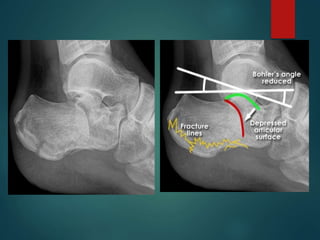

Bohler’s Angle

▪ A line is drawn from the tuberosity to the most superior part

of the posterior facet.

▪ Another line is drawn from the most superior part of the

facet to the anterior process.

Normally the angle created is between 20 and 40 degrees.

▪

▪ If the angle is less than 20 degrees, this indicates depressed

fracture.

The critical angle of Gissane

 It is formed by a line along the lateral margin of the

posterior facet and another line extending anterior to

the beak of the calcaneus. The normal value is 95 to 105

degrees with an increase representing posterior facet

collapse